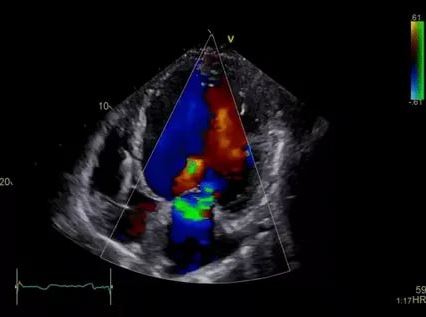

Не требуют специальной подготовки УЗИ сердца, головного мозга, почек и области шеи |